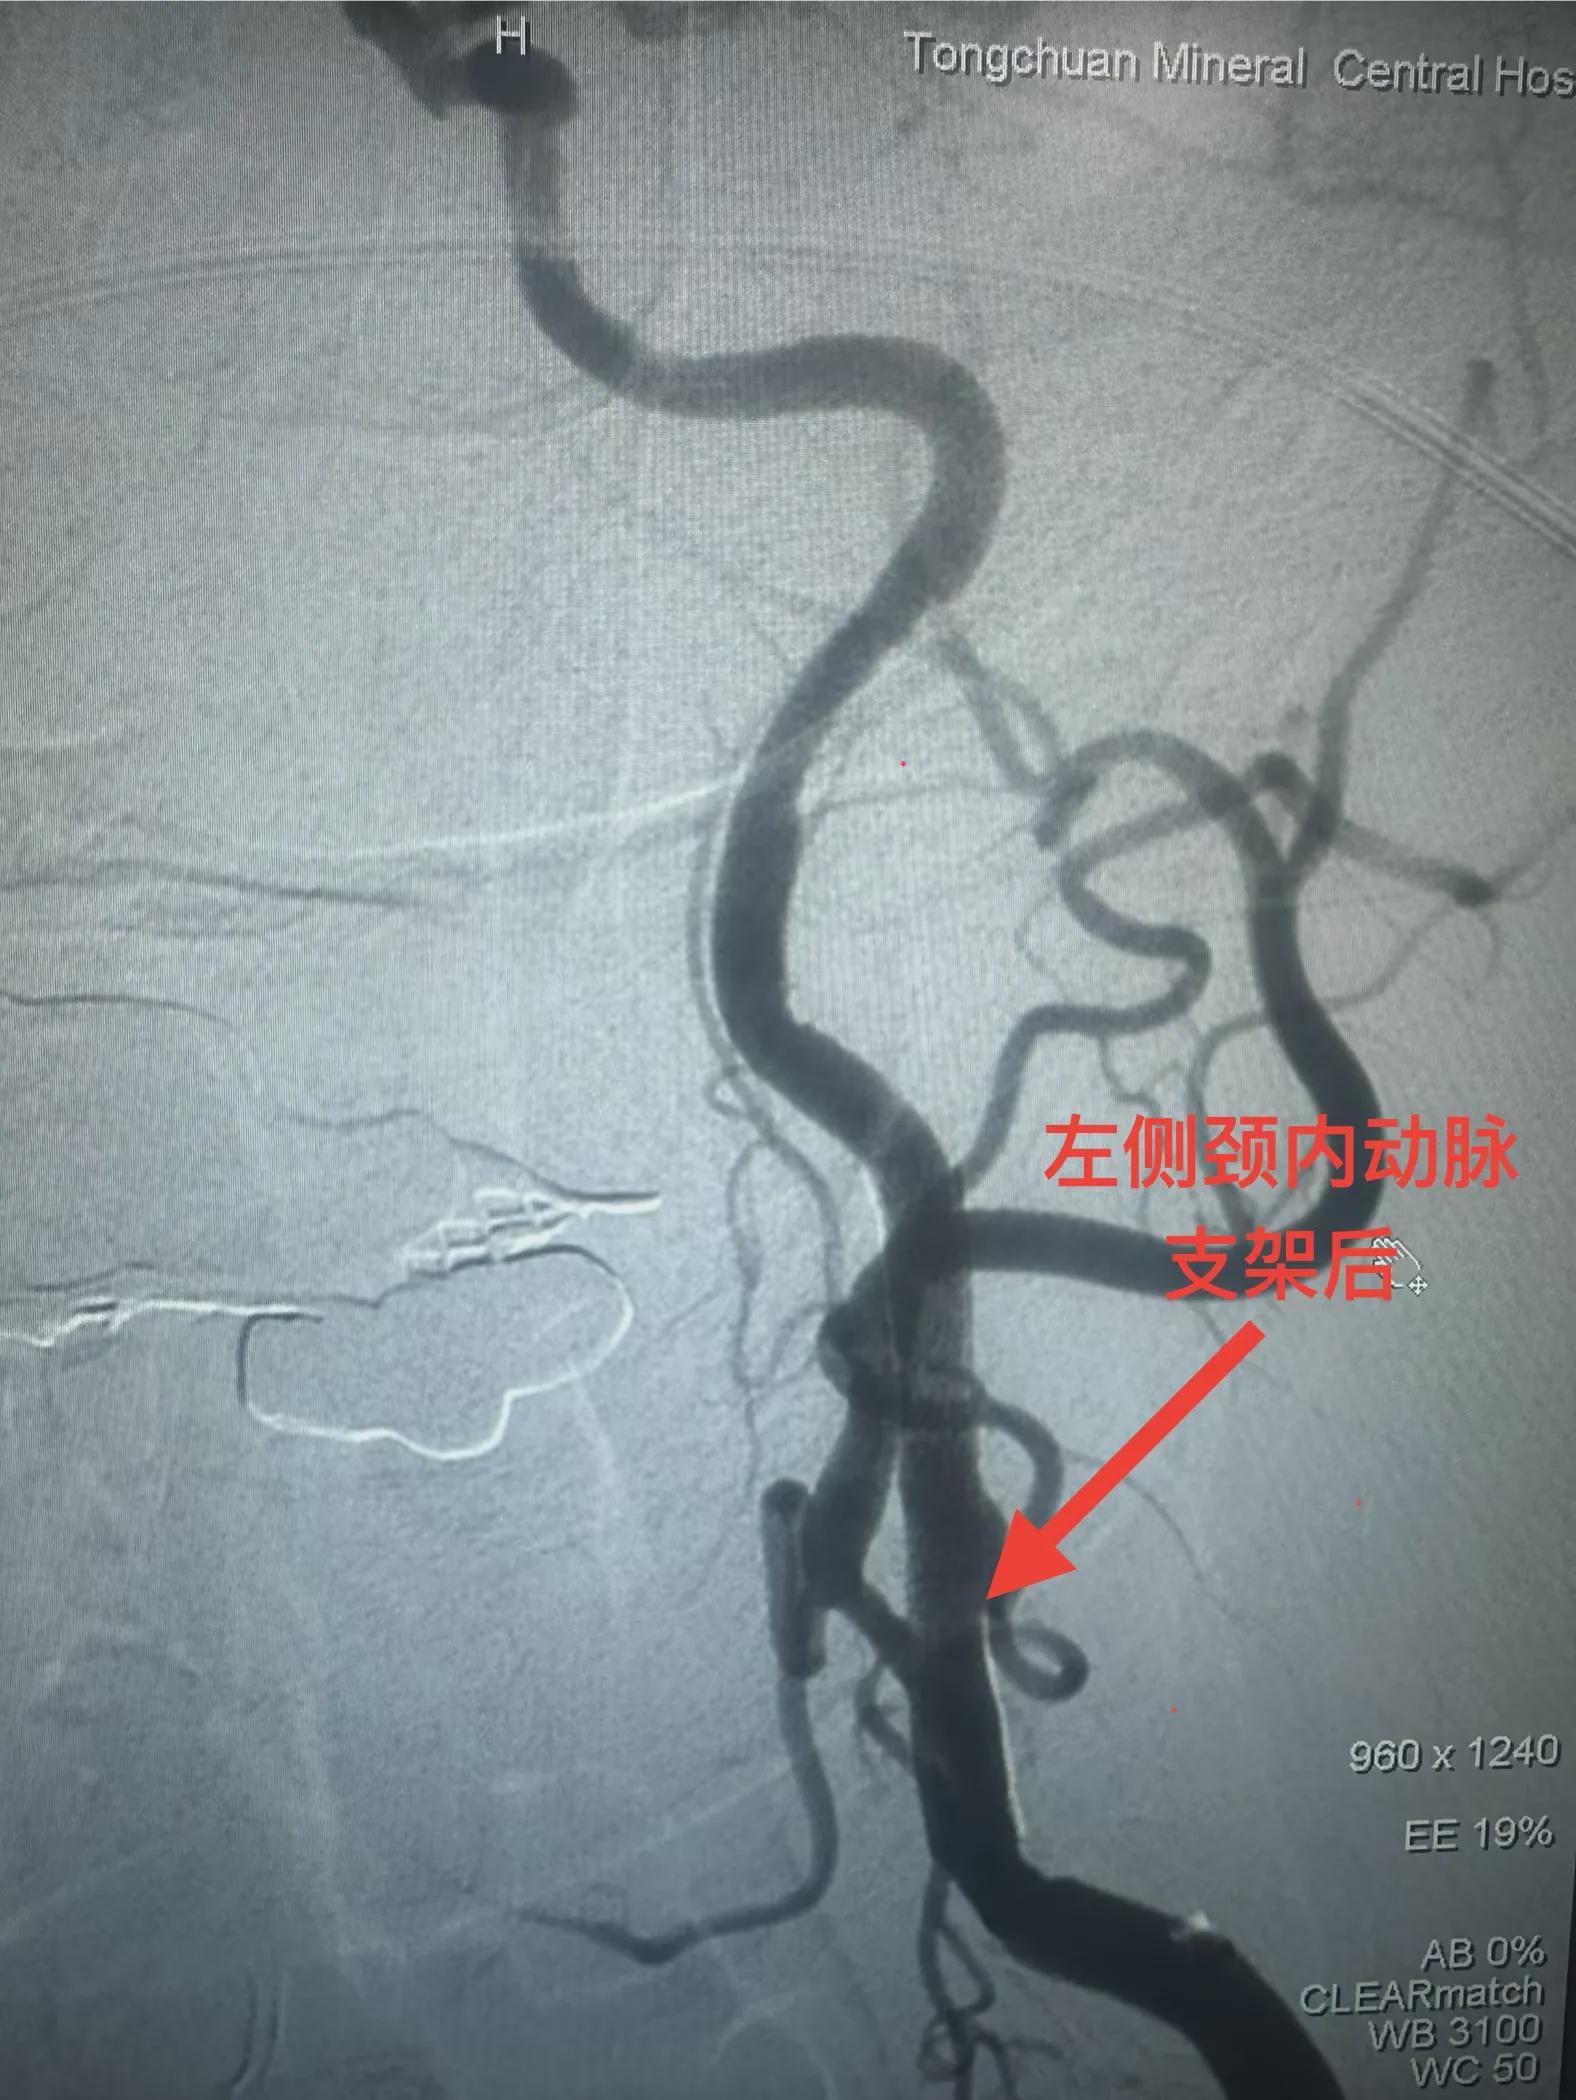

神经内二科团队为患者行球囊扩张手术后,经导引导管将超声诊断导管送至狭窄处远端,连接专用超声诊断仪器后进行了血管腔内超声扫描,清楚显示球囊扩张后血管形态,及血管内膜与斑块破损情况,并在超声诊断基础上,根据血管形态判断,准确置入支架,精准解除了血管狭窄,让患者获得了更为精确的治疗。